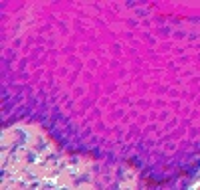

歯科治療の一例

歯科口腔外科用器具による処置 歯肉処置の例

口腔外科に準じた処置 インプラントの埋入手術(上顎)